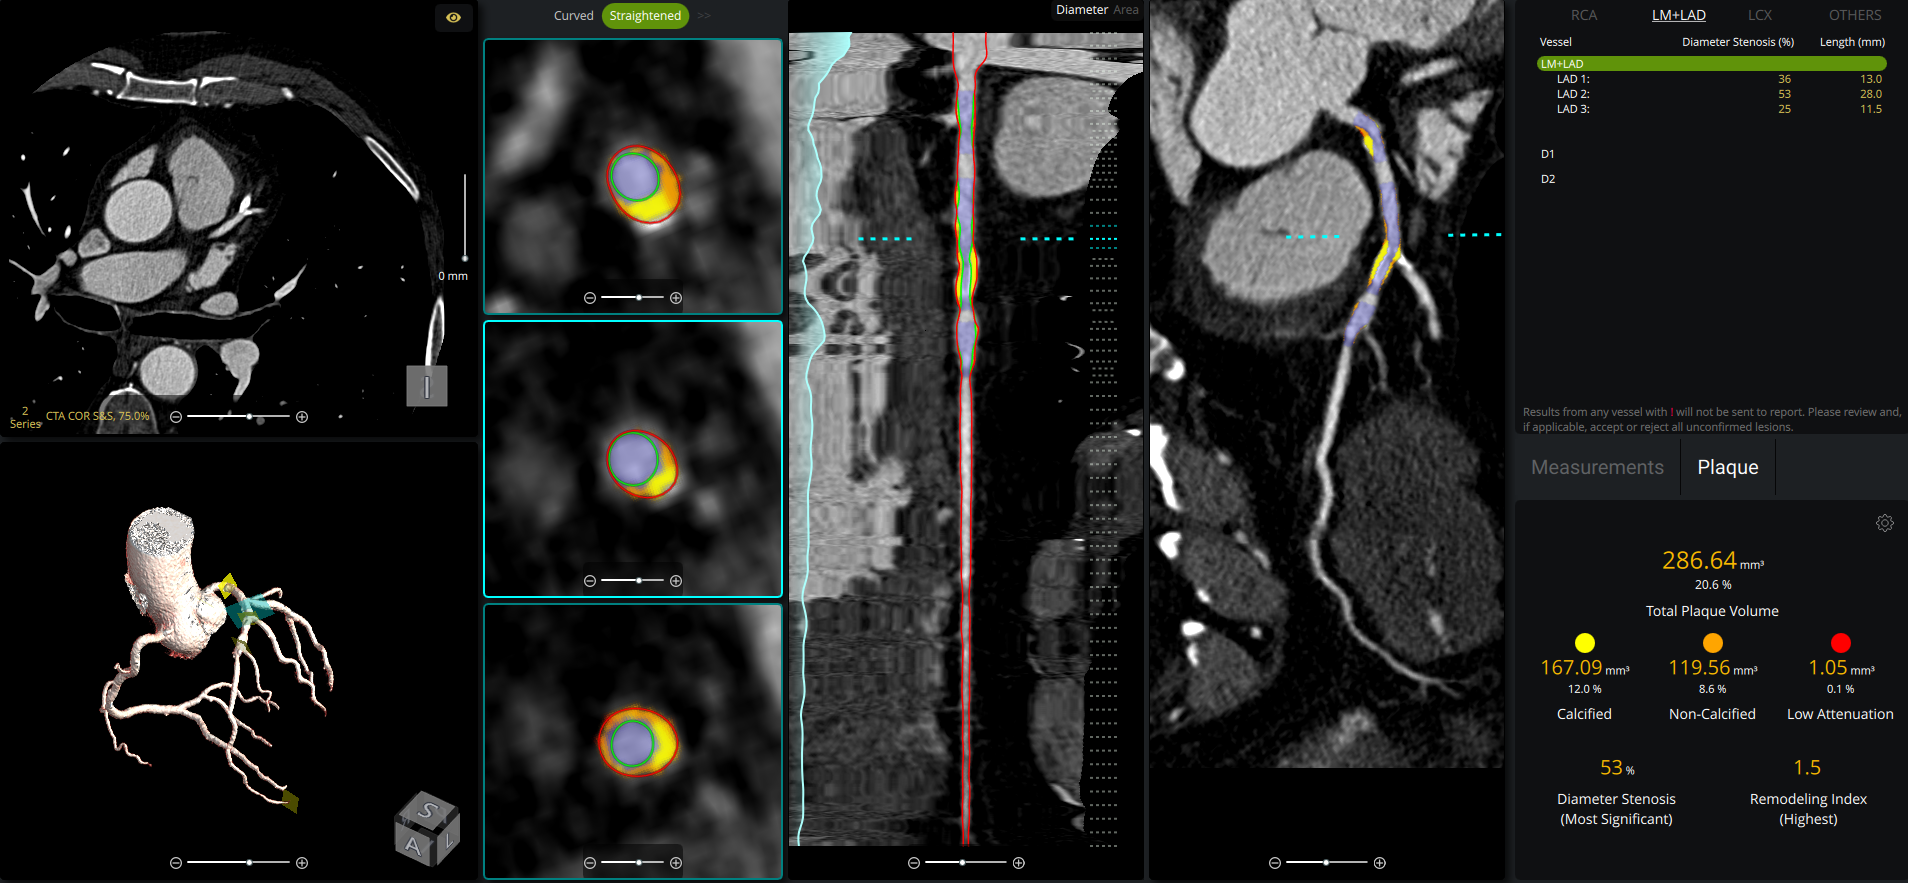

cvi42 | Plaque* empowers cardiac imaging teams with AI-enabled, on-premise quantification of atherosclerotic burden for clinical use. It delivers precise measurements of plaque volume, burden, composition, and distribution, all fully integrated into your CT workflow, without the need to send away to an outside reading service.

- Automated coronary lumen and wall segmentation ensures rapid, reproducible plaque quantification

- Per-lesion and per-vessel analysis provides detailed assessment of calcified, non-calcified, and low attenuation plaque for precise risk stratification

- Remodeling index calculation identifies high-risk plaques beyond stenosis severity

- Manual controls allow adjustment of lumen, vessel wall, and lesion annotations as needed

- Lesion-level occlusion marking enhances detection of chronic total occlusions and supports revascularization planning

- Option of single- or dual-reference markers allows flexibility in grading stenosis